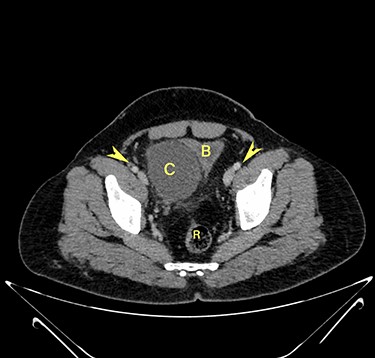

Transverse section image of a contrast-enhanced CT scan of the abdomen at the level 4–4 (Fig. 1), showing a solitary cyst (C) with a non-enhancing wall separate from the urinary bladder (B). Iliac vessels are labelled with arrowheads.